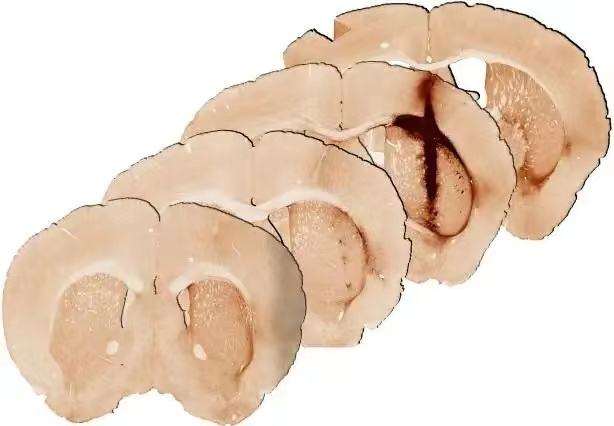

最新研究在受伤的小鼠脑组织中展开,团队证实,结合了肌红蛋白和干细胞的水凝胶,修复了受伤的脑组织。与不含肌红蛋白的水凝胶相比,健康大脑功能所需的新干细胞,存活和生长都显著增强。

该研究提高了未来在人体治疗中生长新组织的可能性,这也是水凝胶中实现氧气输送和干细胞移植长期存活的第一个证据。